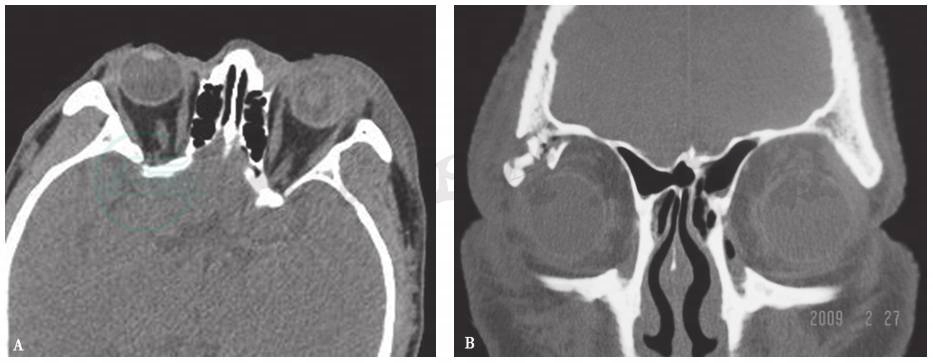

1.CT表现

泪腺肿胀、轮廓不清、密度增高或不均匀,多伴有局部眼睑肿胀,有时可见碎骨片(图1)。

图1眼睑泪腺外伤的CT检查

A.眼眶横轴位软组织窗CT:左侧泪腺体积增大,密度不均;左眼睑软组织影增厚;左眼玻璃体密度增高;B.眼眶冠状位骨窗CT:右眼眶外上方眶缘粉碎性骨折,泪腺区多发骨碎片